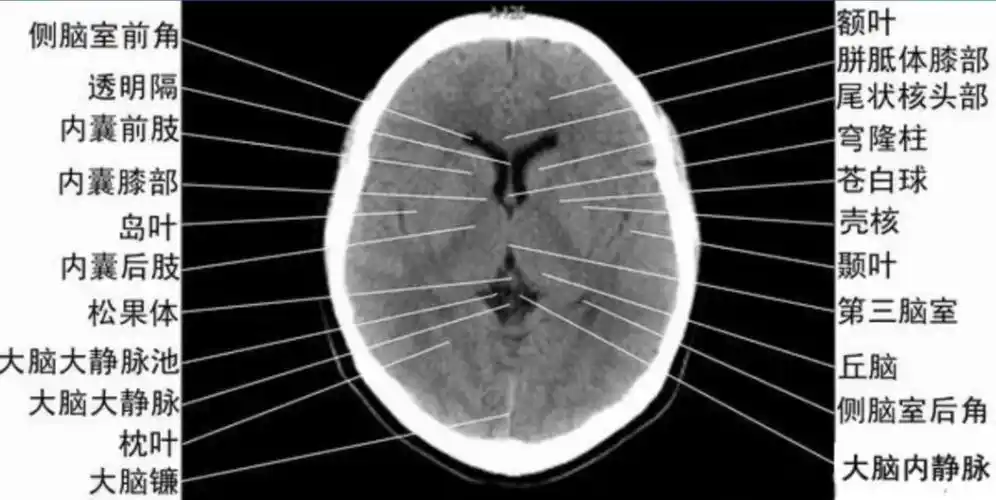

头颅ct 解剖图谱,人手一份

颅脑ct的正常解剖